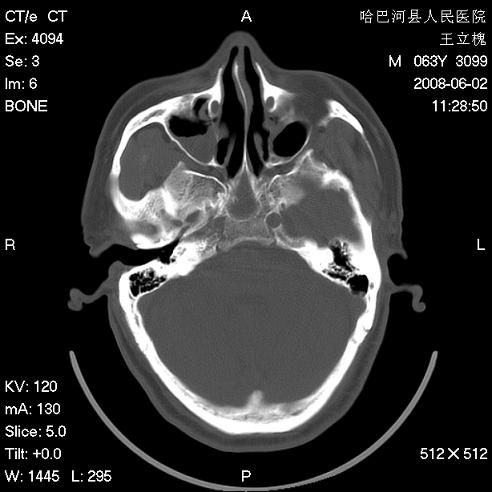

标题: CT13803:反复性鼻塞、流涕一年余 [打印本页]

标题: CT13803:反复性鼻塞、流涕一年余

副鼻窦炎,右上额窦积脓。左眼肌锥内见致密影,视神經受压

1.全组副鼻窦炎2.双侧上颌窦积液

1)全副鼻窦炎(左侧上颌窦黏膜下囊肿或息肉)。2)左眼眶肌锥内不规则小结节状软组织密度影;考虑为小血管瘤可能。建议行ct增强扫描检查。

全组副鼻窦炎,左侧肌锥内不规则形软组织肿块影,与眼外肌密度相当,左侧视神经受压,肿块与视神经及眼外肌分界清晰,眼外肌无增粗,眶壁无破坏,球后脂肪间隙不模糊,考虑良性改变,小血管瘤或神经源性肿瘤可能,建议增强扫描。

谢谢,增强扫描做了,眶内病灶与海绵窦同步明显强化,血管瘤